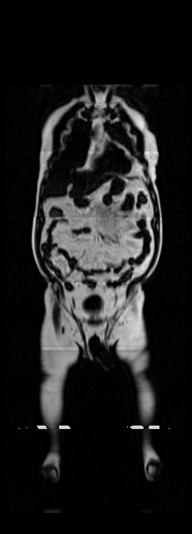

Notably, X-Diffusion achieves state-of-the-art dB for a few input slices while baselines require more than 60 input slices to achieve similar performance (Figure 7). The margin is more than 12 dB PSNR for the 1-slice input in both the BRATS and the UK Biobank benchmarks (see Table 1 and Figure 6). For reference, two randomly sampled MRIs from UK Biobank would have a PSNR of 15.95 dB 0.36 (on 4800 randomly sampled examples). Omitting the preprocessing step of alignment DXA to MRI, leads to a drop of PSNR on average by 2.87 dB (29.01 dB 26.14 dB). The slices from 3D reconstructed volumes at varying depths and axis of rotation, visually match the ground truths for both brain and whole-body scans (see Figures 4 and 5 left). We also plot the error map (Figure 3) and the spread of the error (Figure 5 right) of such X-Diffusion generations to highlight the differences with the ground truth MRIs.

Preservation of Spine Curvature. For the spine segmentation on UK Biobank, we use a UNet++ model [83] with Dice Loss. We use a model trained to predict curves on DXA on UK Biobank [11]). We measure the Pearson correlation factor [11] of spine curvature measured on the generated MRIs where the input is a single MRI coronal slice, a single sagittal slice, or from the paired DXA, against the curvature of reference real MRIs of the same samples. The correlation coefficients are 0.89 for the coronal MRIs, 0.88 for the sagittal MRIs, and 0.87 for the DXAs on the test set of 308 human-annotated angles. We can then bin the curvature of the spines under different scoliosis categories based on human-annotated angles: mild: , moderate: , and severe . We show the results in Figure 8. This illustrates that the generated MRIs preserve the spine curvature from normal to severe scoliosis cases. Additional details about spine curvature are provided in supplementary material.